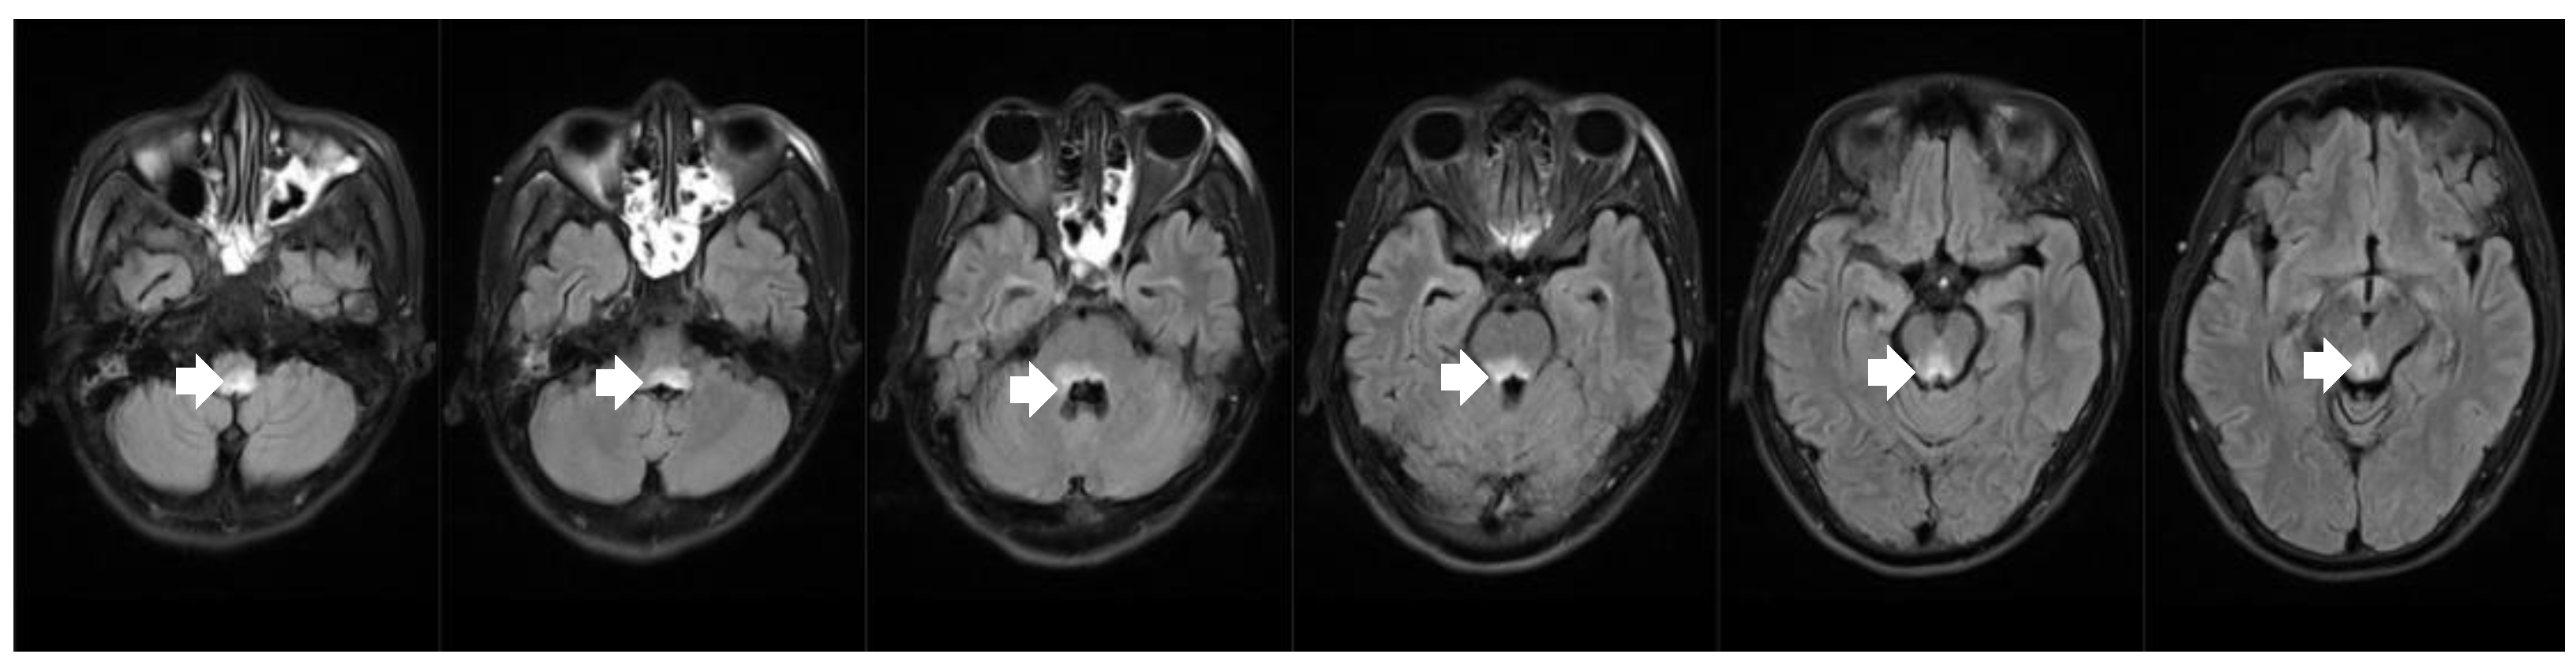

Figure 2.

Brain MRI revealed bilateral high-intensity lesions in the dorsal part of the medulla oblongata on axial fluid attenuated inversion recovery (FLAIR) sequence.

Brain MRI showed new lesions in the dorsal part of the medulla oblongata, pons, and mesencephalon (Figure 3). A serum anti-aquaporin 4 antibody test was positive. Based on typical brainstem syndrome manifestations, the presence of periependymal brain stem lesions in MRI, and the positive AQP4 antibody test, this patient was definitively diagnosed with NMOSD. After readmission, the patient was referred to the ICU due to aspiration pneumonia caused by dysphagia, as well as the recurring hiccups and vomiting. After strong anti-infection therapy, the patient’s body temperature returned to normal, and chest CT showed inflammation resorption and improvements in inflammatory factors. Nevertheless, he had a respiratory arrest followed by a subsequent cardiac arrest. He was successfully resuscitated with epinephrine injection and cardiopulmonary resuscitation. Considering the patient’s pulmonary infection was under control, and his symptoms were not consistent with the presentation of septic shock, we attributed the cause of the slow heart rate and low blood pressure to his NMOSD. The patient was treated with one course of intravenous methylprednisolone, one course of therapeutic plasma exchange, and one course of IVIG before his blood pressure and heart rate were stable within the normal range. He was then transferred to another hospital for rehabilitation. After discharge, the patient chose oral steroids and azathioprine as a disease-modifying therapy.

Figure 3.

Brain MRI revealed bilateral high-intensity lesions in the dorsal part of the medulla oblongata, periependymal surfaces of the pons and dorsal midbrain on axial fluid attenuated inversion recovery (FLAIR) sequence.